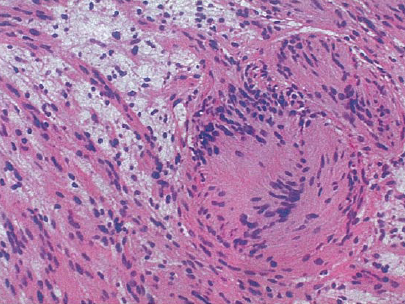

Schwannoma: note the Antoni A (more cellular, palisading nuclei with surrounding pink areas with rows of nuclei in parallel array called Verocay bodies) and Antoni B which has looser stroma, fewer cells, and myxoid change